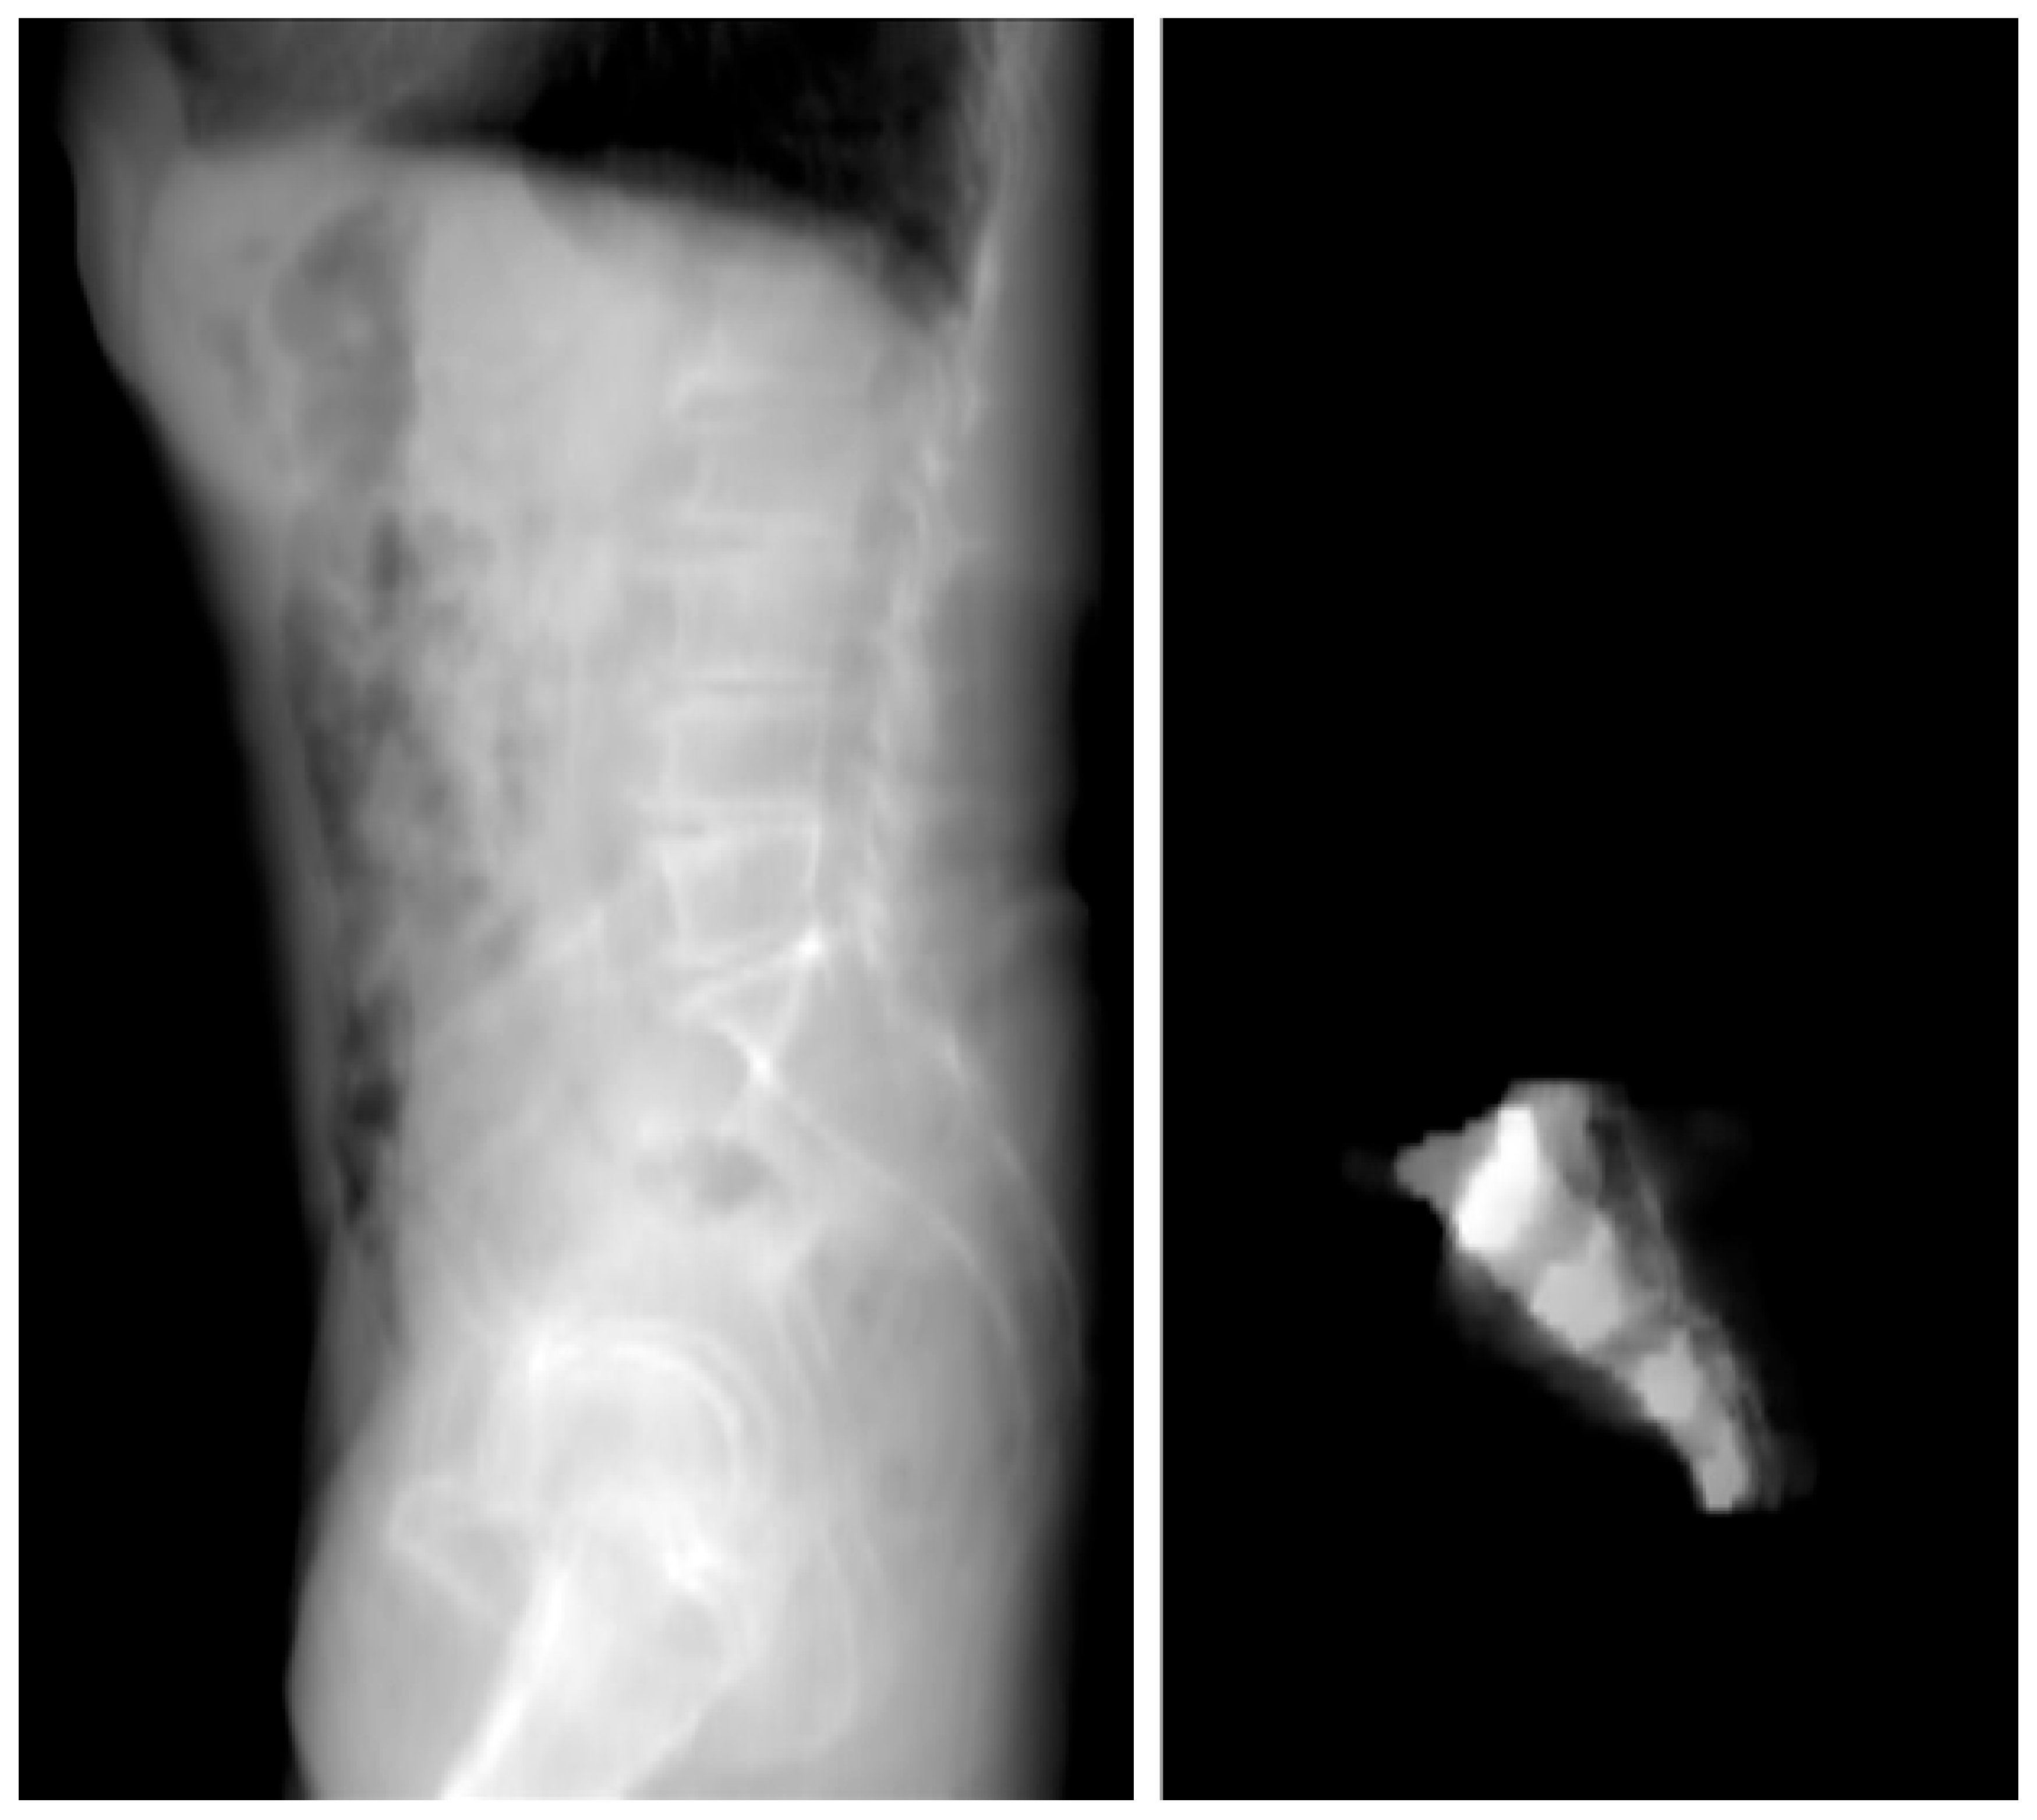

- 2D Projection Creation: From the 3D model, a 2D lateral view of the sacrum was generated by summing the Y-axis slices of the dataset. This 2D projection effectively reflected the bone density distribution within the sacrum and was crucial for visualizing regions of higher bone density. These areas were considered optimal for screw placement, as higher density regions are more likely to provide stable, intraosseous fixation.

3.2. Two-Dimensional Projection Analysis